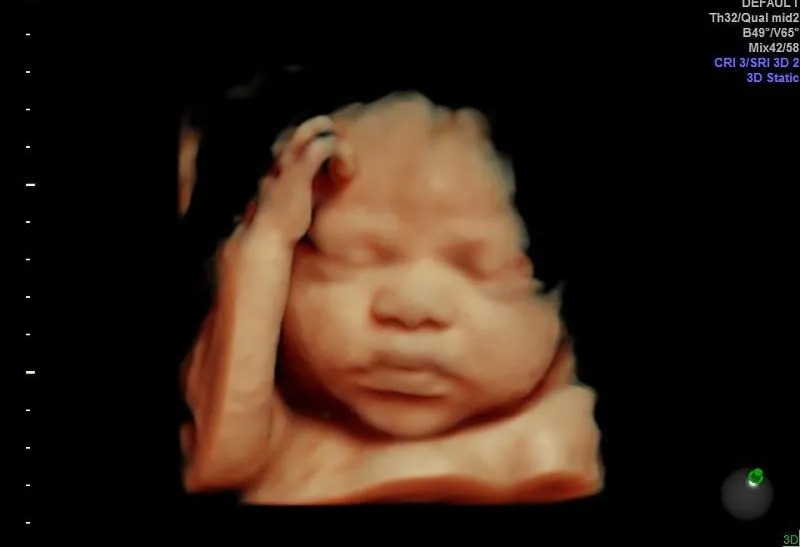

3D 4D HD live pregnancy ultrasound. Early gender determination. Medical diagnostic pregnancy monitoring.